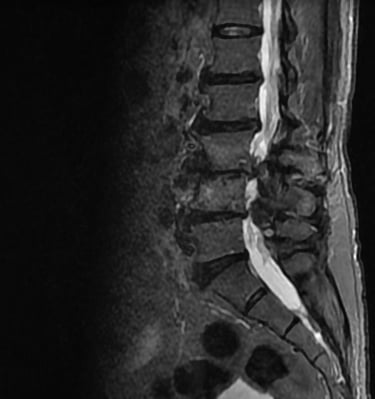

Galería

Momentos que reflejan dedicación y cuidado humano.